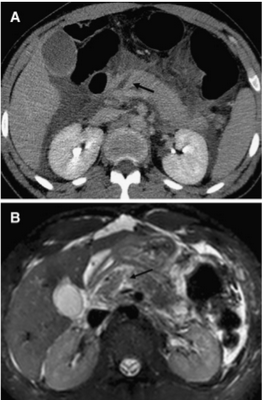

Изображение 5. Разрыв поджелудочной железы IV степени у 41-летнего мужчины, пострадавшего в результате ДТП. На МСКТ (А) показан линейный разрыв (стрелка) в головке поджелудочной железы справа от верхней брыжеечной вены.

На МРТ (В) изображение того же пациента демонстрирует разрыв в головке поджелудочной железы (стрелка).